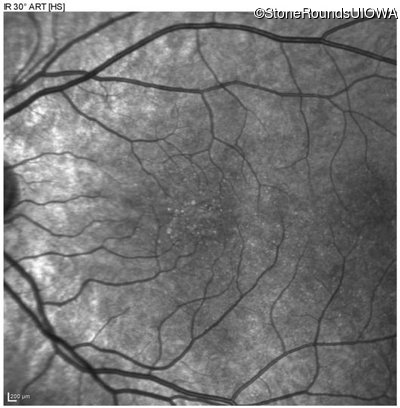

Infrared Fundus Photograph - Left - 20/40 sc

Exemplar